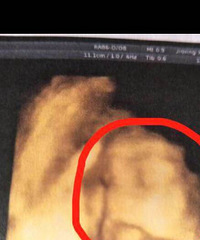

买了根高档验孕棒一测就准

怎么说呢,TA就这么来了从10月开始就处于备用状态因为本身大姨妈就不太正常,自己又比较马虎,过一个星期就会用验孕棒检查一下我们婚期是11月25日,22号准备回家结婚那天检查了一下还是一道杠。想想自己应该就是没怀上,就大大咧咧的回家结婚了。折腾了几天,26号回了嘉兴。27号想